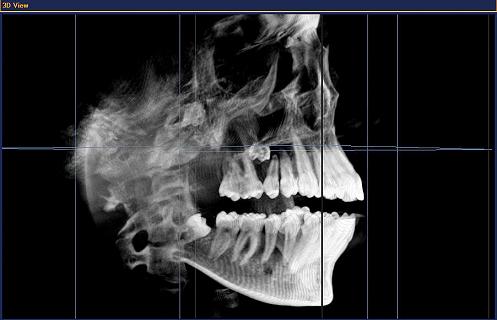

- Трехмерная диагностика для точного анализа костной структуры и всех анатомических структур.

3D-объем GALILEOS

Большой объем размером 1 миллиард вокселей от переносицы до кончика подбородка и челюстных суставов. Отличное отображение костных структур и мягких тканей.

После прохождения короткой реконструкции GALILEOS показывает не только 3D-изображения отличного качества. Большой объем с высоким разрешением деталей отображается при панорамной, цефалометрической и TSA-съемке. Привычный панорамный снимок позволяет интуитивно ставить диагноз в масштабе реального времени.

В 3D-объеме GALILEOS (15х15х15) см3 на панорамном и цефалометрическом снимке можно интуитивно переходить из одного окна в другое и обследовать различные зоны.